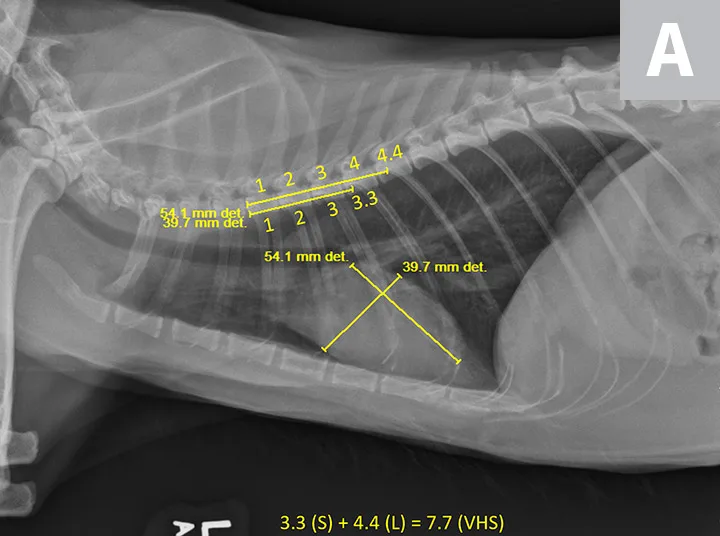

VHS calculation in a cat diagnosed with HCM using a right lateral radiograph (A). L (ie, long axis; 5.0) is drawn from the carina to the most ventral aspect of the apex. S (ie, short axis; 3.5) is drawn perpendicular to L at the widest aspect of the heart, extending to the cranial and caudal borders. S and L are transposed along the spine from the cranial aspect of T4 using calipers. The number of vertebrae traversed (rounded to the nearest tenth) are summed to calculate VHS (8.5). Pulmonary vasculature is prominent but within normal limits, and there is a ballistic metallic foreign body (likely a bullet) in the dorsal subcutaneous tissue of the caudal thorax. Moderate spondylosis deformans exists at T13-L1 and L1-L2, and there is bridging spondylosis deformans at T10-T11. Intervertebral disk space at T10-T11 is collapsed, and there is fusion at the 2 vertebral bodies. Orthogonal radiograph of the patient is also shown for more complete evaluation of cardiac silhouette (B).

A 12-year-old neutered male domestic shorthair cat was presented for evaluation of a previously diagnosed heart murmur. On physical examination, a grade III-IV/VI left parasternal systolic murmur was auscultated. All other physical examination findings were within normal limits. There is history of right thoracic limb lameness and mild lytic lesions on the right humerus. Thoracic radiographs revealed mild to moderate cardiac silhouette enlargement with VHS 8.5, suggestive of cardiac disease (Figure 2). Additional cardiac diagnostic investigation (eg, total thyroxine, echocardiography) is recommended, and medical treatment should be considered.